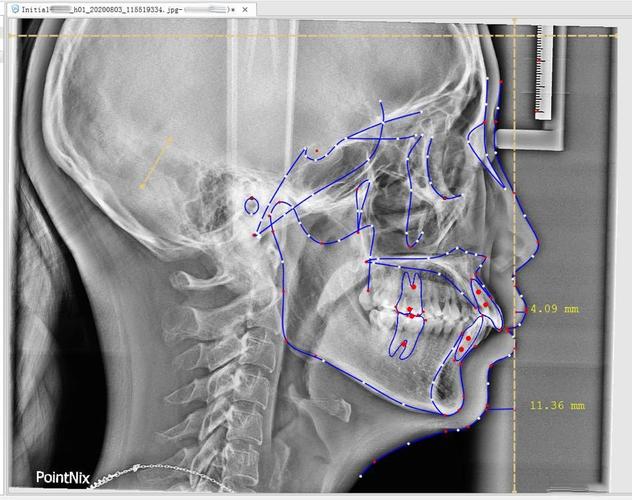

头颅侧位片

头颅侧位片是正畸诊断的“黄金标准”,需在患者头部固定于标准定位仪下拍摄,显示头颅侧面的骨骼、牙齿及软组织轮廓,医生通过在影像上标记标志点(如蝶鞍点、鼻根点、上齿槽座点等),进行一系列角度和距离测量,分析骨骼与牙齿的协调性。

核心测量指标:

- 骨骼关系:ANB角(上齿槽座点与鼻根点连线和下齿槽座点与鼻根点连线的夹角,判断上下颌骨前后向关系);SN-MP角(前颅底平面与下颌平面的夹角,反映下颌平面倾斜度,判断面部垂直高度)。

- 牙齿位置:U1-SN(上前牙切端至SN平面的距离,评估上前牙突度);L1-MP(下前牙切端至下颌平面的距离,评估下前牙直立度)。

适用场景:骨性错颌畸形(如上颌前突、下颌后缩、开颌)的诊断;制定拔牙方案(通过测量牙量与骨量的不匹配程度);预测治疗后面部软组织变化。